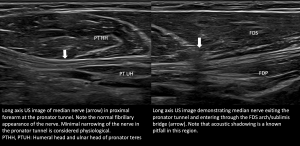

Elbow and Forearm: The median nerve then enters the cubital fossa and courses beneath the bicipital aponeurosis, aka lacertus fibrosus, medial to the brachial vessels. In the proximal forearm, it passes between the humeral and ulnar heads of the pronator teres (PT), forming the pronator tunnel. After exiting the pronator teres, it then enters under the flexor digitorum superficialis (FDS) fibrous arch, aka the sublimis bridge. It then traverses between the flexor digitorum superficialis (FDS) and flexor digitorum profundus (FDP) musculature [3-5].

The median nerve appears round to ovoid in the short axis plane with hypoechoic internal fascicles against a background of hyperechoic interfascicular epineurium, which in turn is surrounded by an external echogenic epineurium giving it a honeycomb appearance. In the long axis, the nerve has a fibrillary pattern. No increased vascularity is demonstrated on the Doppler study [3,5].